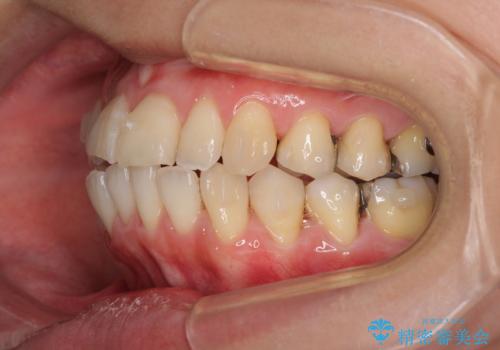

- 前歯のデコボコを気にして来院された患者様です。

上下前歯の先端同士が接触する切端咬合であったため、上顎は歯列を拡大し、下顎はIPR(歯と歯の間を削る)により叢生を解消しながら歯列を小さくすることとしました。

矯正装置にはインビザラインを用いることとしました。

治療途中に前歯に歯髄充血を思わせる痛みが認められたため、無理のない歯の移動と頻繁な経過観察を行いました。

切端咬合はスムーズに解消され、前歯の負担を軽減させることができました。